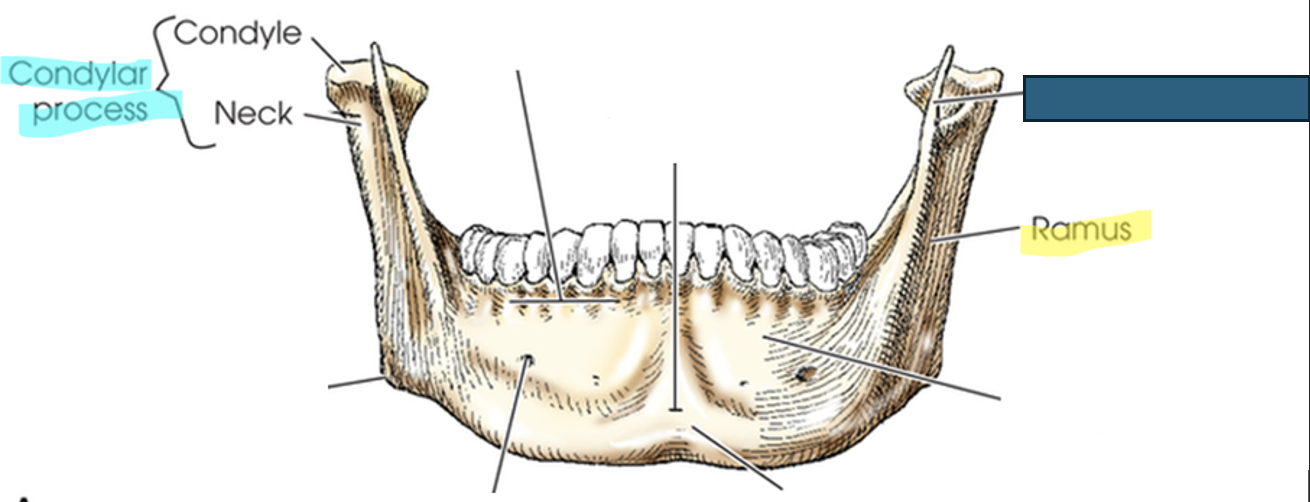

mandible

largest and densest bone of the face

single bone, but at birth to approximately 1 year of age it is 2 bones that eventually fuse

body: curved horizontal portion

what anatomy is this?

symphysis

body

rami (ramus)

two vertical portions on each side of body; terminates in “U” shaped notch

mandibular notch

concave area at top of ramus

each have two processes

coronoid process

condylar process

ramus

anterior process on top of ramus; serves for muscle attachment– can’t be easily felt

condylar (condyloid) process

posterior process that forms TMJ, only movable skull joint.

neck

condyle

angle of mandible (gonion)

where body and ramus meet

most anterior and central part where left and right halves of mandible fuse

alveolar portion (process)

superior border of body; consists of spongy bone that supports roots of teeth

mental foramina

small openings on each side; transmit nerves and blood vessels (for lower teeth)

mental protuberance

anterior, triangular prominence